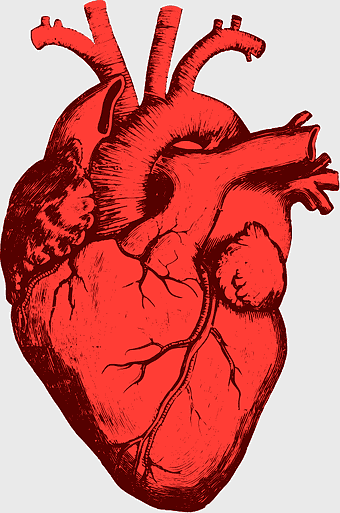

red heart anatomy, human heart drawing, cartoon heart illustration, love and biology, cardiovascular system diagram, medical art depiction, organ structure visualization -

human heart anatomy, cardiac muscle illustration, circulatory system model, heart health visual, cardiovascular organ diagram, medical heart image, visceral structure depiction -

Heart Anatomy Drawing, human heart illustration, human anatomy art, organ depiction, cardiovascular system, medical illustration, anatomical sketch -